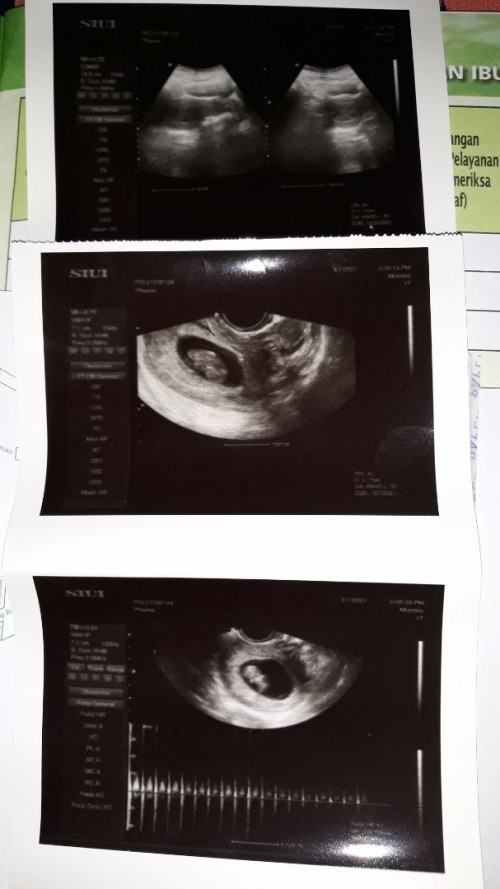

ini aku 8week bund, detaknya juga sudah ada.. tp kembali lagi, setiap kehamilan beda2 bund. tetep semangat dan selalu afirmasi positif ke diri sendiri dan ke janin🤗

ini hasil usgku 4 week bun dah ada bakal embrio ..tpi usg t4 dr dan transvagina. .eh semalam usg t4 bidan 8week cuma ada kantong ..lngsung sedih dna kepikiran

dan ini usg ku 12w. udh ada janin, pas ke bidan uk 11w jg udh ada djj nya.. jd ttp positif dan mkn mknn yg bergizi ya. asam folat jgn lupa